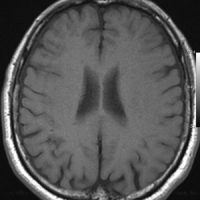

海綿状血管腫のMRI

海綿状血管腫はMRIの撮影条件によっていろいろな見え方をします

腫瘍から少し出血したために,患者さんはけいれん(てんかん発作)を起こしました。左のT1強調画像では出血を疑います。中央のT2強調画像では海綿状血管腫の周りに脳浮腫があるために白くぼやけた部分があります。右の造影剤を使ったMRIでは造影剤が入るところがほどんど無いことがわかります。側頭葉の海綿状血管腫は側頭葉てんかんという症状で発症することが多いです。

出血が溶けて少し小さくなっています。海綿状血管腫の周りには黒い縁取りがあります。この黒い部分は血液が溶けて残った鉄が脳の中にたまったことを示しています(siderosisといいます)。この鉄のしみ込みはけいれんの原因になると考えられます。この海綿状血管腫は中等度の大きさですが,治療が難しいほどのてんかんが無ければ手術などしないでほっておいてもいいです。手術で側頭葉(特に海馬)を損傷すると記憶の障害などもでます。